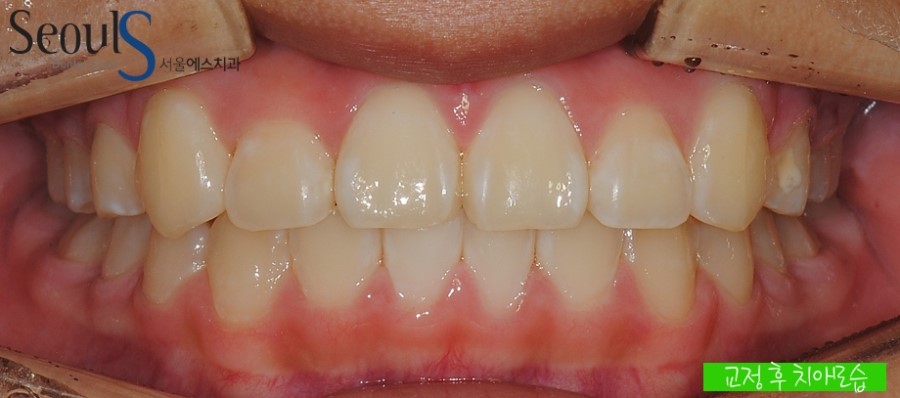

교정 후 정면모습입니다

교정 전, 삐뚤었던 치아가 가지런해진 모습입니다

보시는 것처럼 교정을 통해서 삐뚤었던 치아를 가지런하고 예쁘게 치료할 수 있습니다

이것이 교정을 하는 이유가 아닐까 생각해봅니다